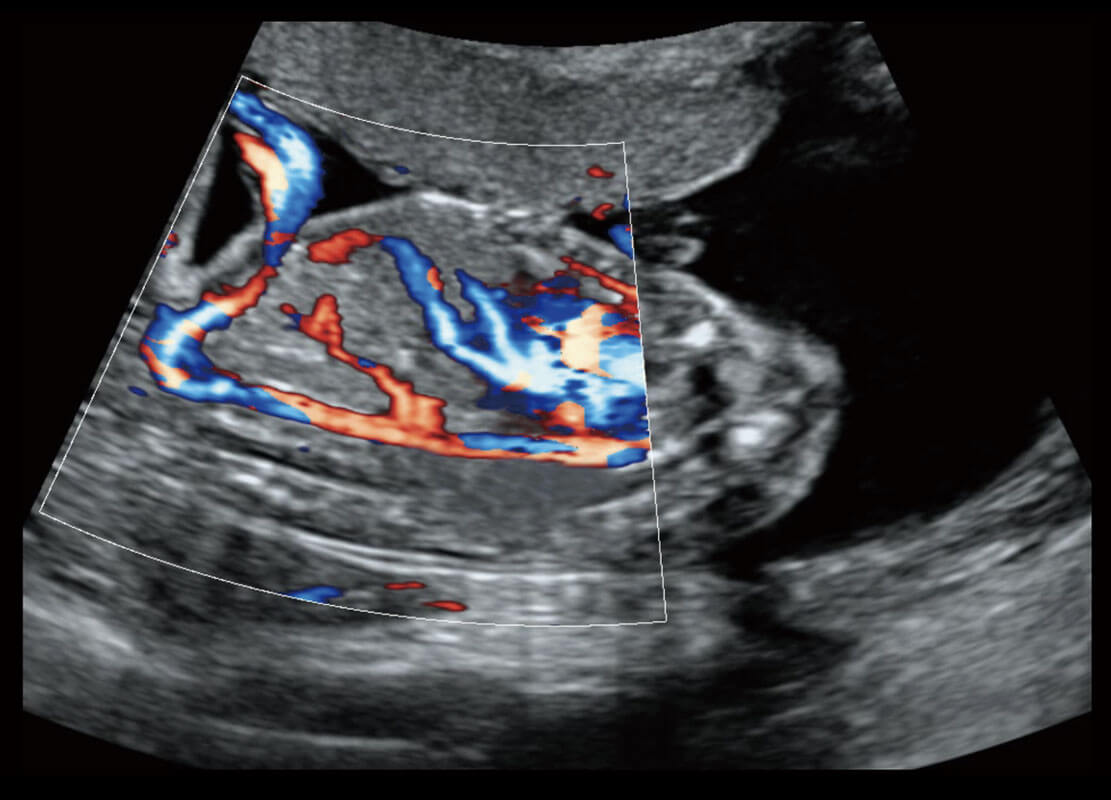

腔内妇科-卵巢

腔内三维-宫内节育器